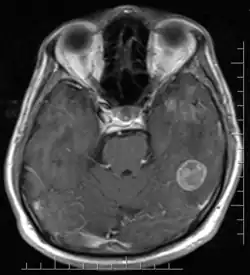

Il existe des différences entre les hommes et les femmes au niveau de certaines structures cérébrales[40]:

- Les femmes ont un pourcentage plus important en matière grise que les hommes[40];

- Les hommes ont un pourcentage plus important en matière blanche que les femmes, à l'exception de certaines régions cérébrales comme le splénium du corps calleux qui est plus important chez la femme[40];

- La zone appelée SDN-POA (sexually dimorphic nucleus (SDN) dans l'aire préoptique médiane (POA), ainsi que INAH3 qu'elle comprend, située dans l'aire pré-optique de l'hypothalamus, est d'une taille significativement plus grande chez l'homme que chez la femme. "Personne ne sait encore ce que fait cet amas de cellules" reconnaît Rebecca Jordan-Young[41].

- Il existe une asymétrie cérébrale plus importante chez les hommes que chez les femmes pouvant expliquer les meilleures performances des hommes dans les épreuves visuo-spatiale[40];

- À l'inverse, il existe une symétrie bilatérale plus importante chez la femme qui pourrait rendre compte de leur meilleure performance dans le domaine verbal[40]. Une étude d'imagerie par résonance magnétique fonctionnelle menée sur des enfants s'est intéressée au traitement neuronal et a montré les différences suivantes : l’activation chez les filles bilatéralement dans les gyrus frontal inférieur, gyrus temporal supérieur et gyrus fusiforme gauche est plus grande dans les 4 tâches (jugement orthographique auditif ou visuel, jugement phonologique auditif ou visuel)[42]. En revanche, la plus grande activation dans le gyrus temporal supérieur se limite aux tâches auditives[42]. L’activation du cerveau dans le gyrus occipital inférieur et dans le gyrus temporal moyen gauche est corrélée à la performance d’exactitude dans les 2 tâches, ce qui n’est pas le cas chez les garçons[42]. Chez eux, la corrélation avec l’exactitude se fait avec la modalité de présentation du mot : pour les mots audibles, c’est la région frontale inférieure qui est activée, tandis que pour les mots visibles, c’est l’activation du lobe pariétal supérieur gauche et le précuneus qui entrent en jeu[42].